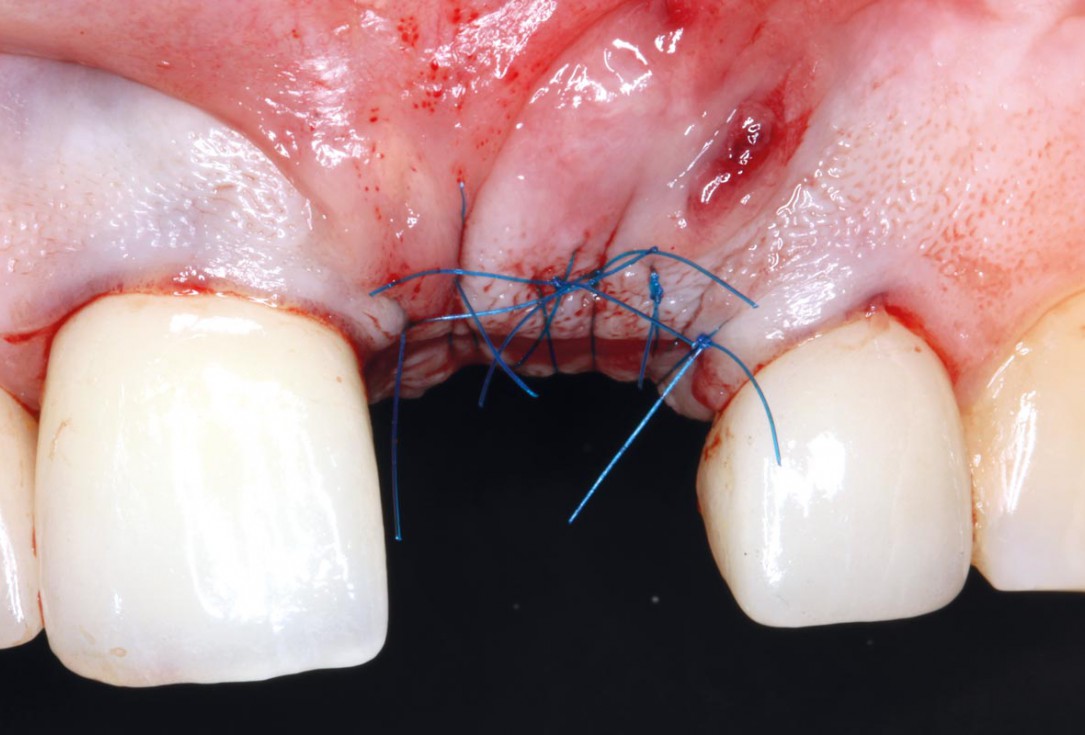

06/10 - Suturing; mucoderm® partially left exposed

Socket augmentation using mucoderm®, maxgraft® and Straumann® Emdogain® - Dr. A. Puišys